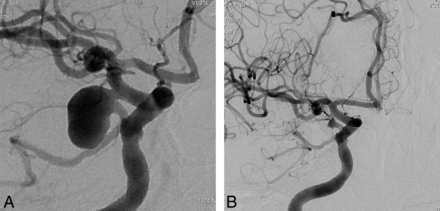

This retrospective study included 251 aneurysms treated with PEDs in 191 consecutive patients (mean age, 49.2 years; age range, 26–71 years; except for 1 pediatric patient who was 13 years of age) between November 2008 and September 2011. One hundred twenty-nine patients were female and 62 were male. Following ethics committee approval, 17 of the patients were included in the Pipeline for Uncoilable or Failed Aneurysms Study. Written informed consent was obtained from each patient. Sidewall aneurysms with wide necks (≥4 mm) or unfavorable dome-neck ratios (≤1.5) (Fig 1), large or giant aneurysms that might have or already had mass effect (Fig 2), fusiform aneurysms (Fig 3), blisterlike aneurysms (Fig 4), recurrent sidewall aneurysms, dissecting aneurysms (Fig 2), aneurysms at difficult angles to the parent artery (so that catheterization of the aneurysm and coiling may have increased risk) (Fig 5), and aneurysms in which a branch was originating directly from the sac (therefore endosaccular obliteration or clipping was likely to compromise the branch or result in a neck remnant) were treated with the PED (Figs 6 and 7). We intended to treat 1 patient with a giant, very wide-neck, cavernous ICA aneurysm presenting with mass effect symptoms by using a PED; however, we failed to bypass the neck of the aneurysm, resulting in treatment of the aneurysm with parent artery occlusion following a balloon occlusion test, without complications. This patient was not included in the study because a PED was not used. This was the only technical failure during the course of the series.

Preoperative 2D (A and B) angiograms show the ICA aneurysm in which the anterior choroidal artery is originating from the aneurysm at the neck. A single PED is placed covering the neck, causing stagnation of the contrast within the sac (C). Six-month control angiography (D) demonstrates total occlusion of the aneurysm with the anterior choroidal artery preserved (arrow).

Right internal carotid oblique angiogram (A) shows a right posterior communicating artery aneurysm (the ipsilateral P1 is aplastic and not shown) in a patient in whom previous endovascular attempts and clipping had failed, with surgical wrapping performed eventually. Two years after a single PED placement, the aneurysm is remodeled in the corresponding view (B).